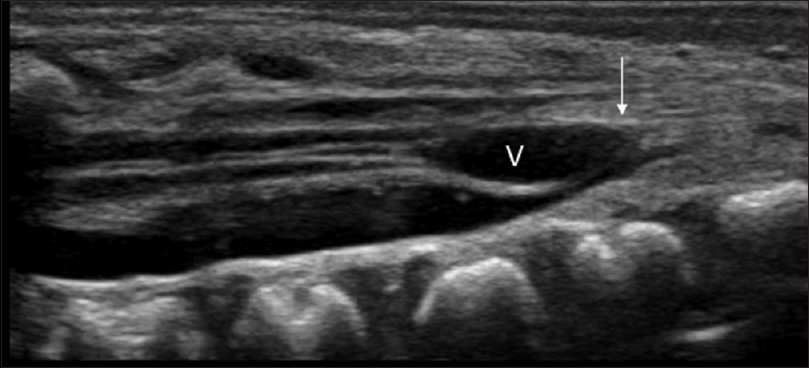

Tethered Cord

Tethered cord is a syndrome with several causes in which the spinal cord is pulled tight due to a mass or dysraphism like spina bifida.

The normal spinal cord moves freely within the spinal fluid filled canal. When there is tethering, the cord can be taut and attached to the vertebral column or subcutaneous tissues by a thickened filum terminale, dermal sinus tract, diastematomyelia (split cord), or a lipoma.

When this is present the conus medullaris will be located below L2, it can be located at L4 and even lower in more severe cases.